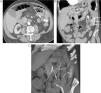

Paciente intervenido de neoplasia esofágica y reconstrucción mediante coloplastia, que presenta hematemesis. A) Reconstrucción coronal de TC que muestra un pseudoaneurisma (flecha gruesa) adyacente a la sonda de alimentación (flecha fina). B) La reconstrucción «volume rendering» demuestra el pseudoaneurisma (flecha gruesa) dependiente de una rama de la arteria cólica media (flechas finas). C) La arteriografía guiada por los hallazgos de la TC confirma la existencia del pseudoaneurisma (flecha), con posterior embolización del mismo.

Sangrado digestivo en un paciente portador de una derivación bilioentérica. A) Corte axial de TC que muestra la presencia de coágulos en el asa yeyunal de la derivación (flecha fina) y una imagen de pseudoaneurisma en la anastomosis (flecha gruesa). B) Reconstrucción curva que permite ver la zona de la anastomosis, coágulos intraluminales (flechas finas blancas), el pseudoaneurisma (flecha gruesa blanca) y la dilatación de la vía biliar proximal (flecha negra). C) Reconstrucción «volume rendering» que muestra el origen de la arteria hepática en la mesentérica superior (flecha fina) y el pseudoaneurisma dependiente de la arteria hepática derecha (flecha gruesa). D) La arteriografía confirma estos hallazgos (pseudoaneurisma, flecha gruesa) y visualiza el sangrado activo al asa yeyunal durante la exploración (flechas finas). Se realizó la embolización del pseudoaneurisma con espirales, con preservación de la vascularización hepática y cese del sangrado.